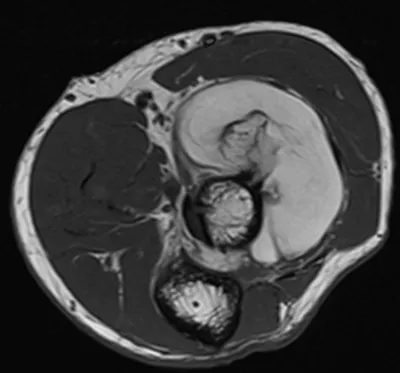

- This collection contains 4 radiology images related to forearm, including various imaging modalities such as X-rays, MRIs, CT scans, and ultrasound images commonly used in medical diagnosis and education.